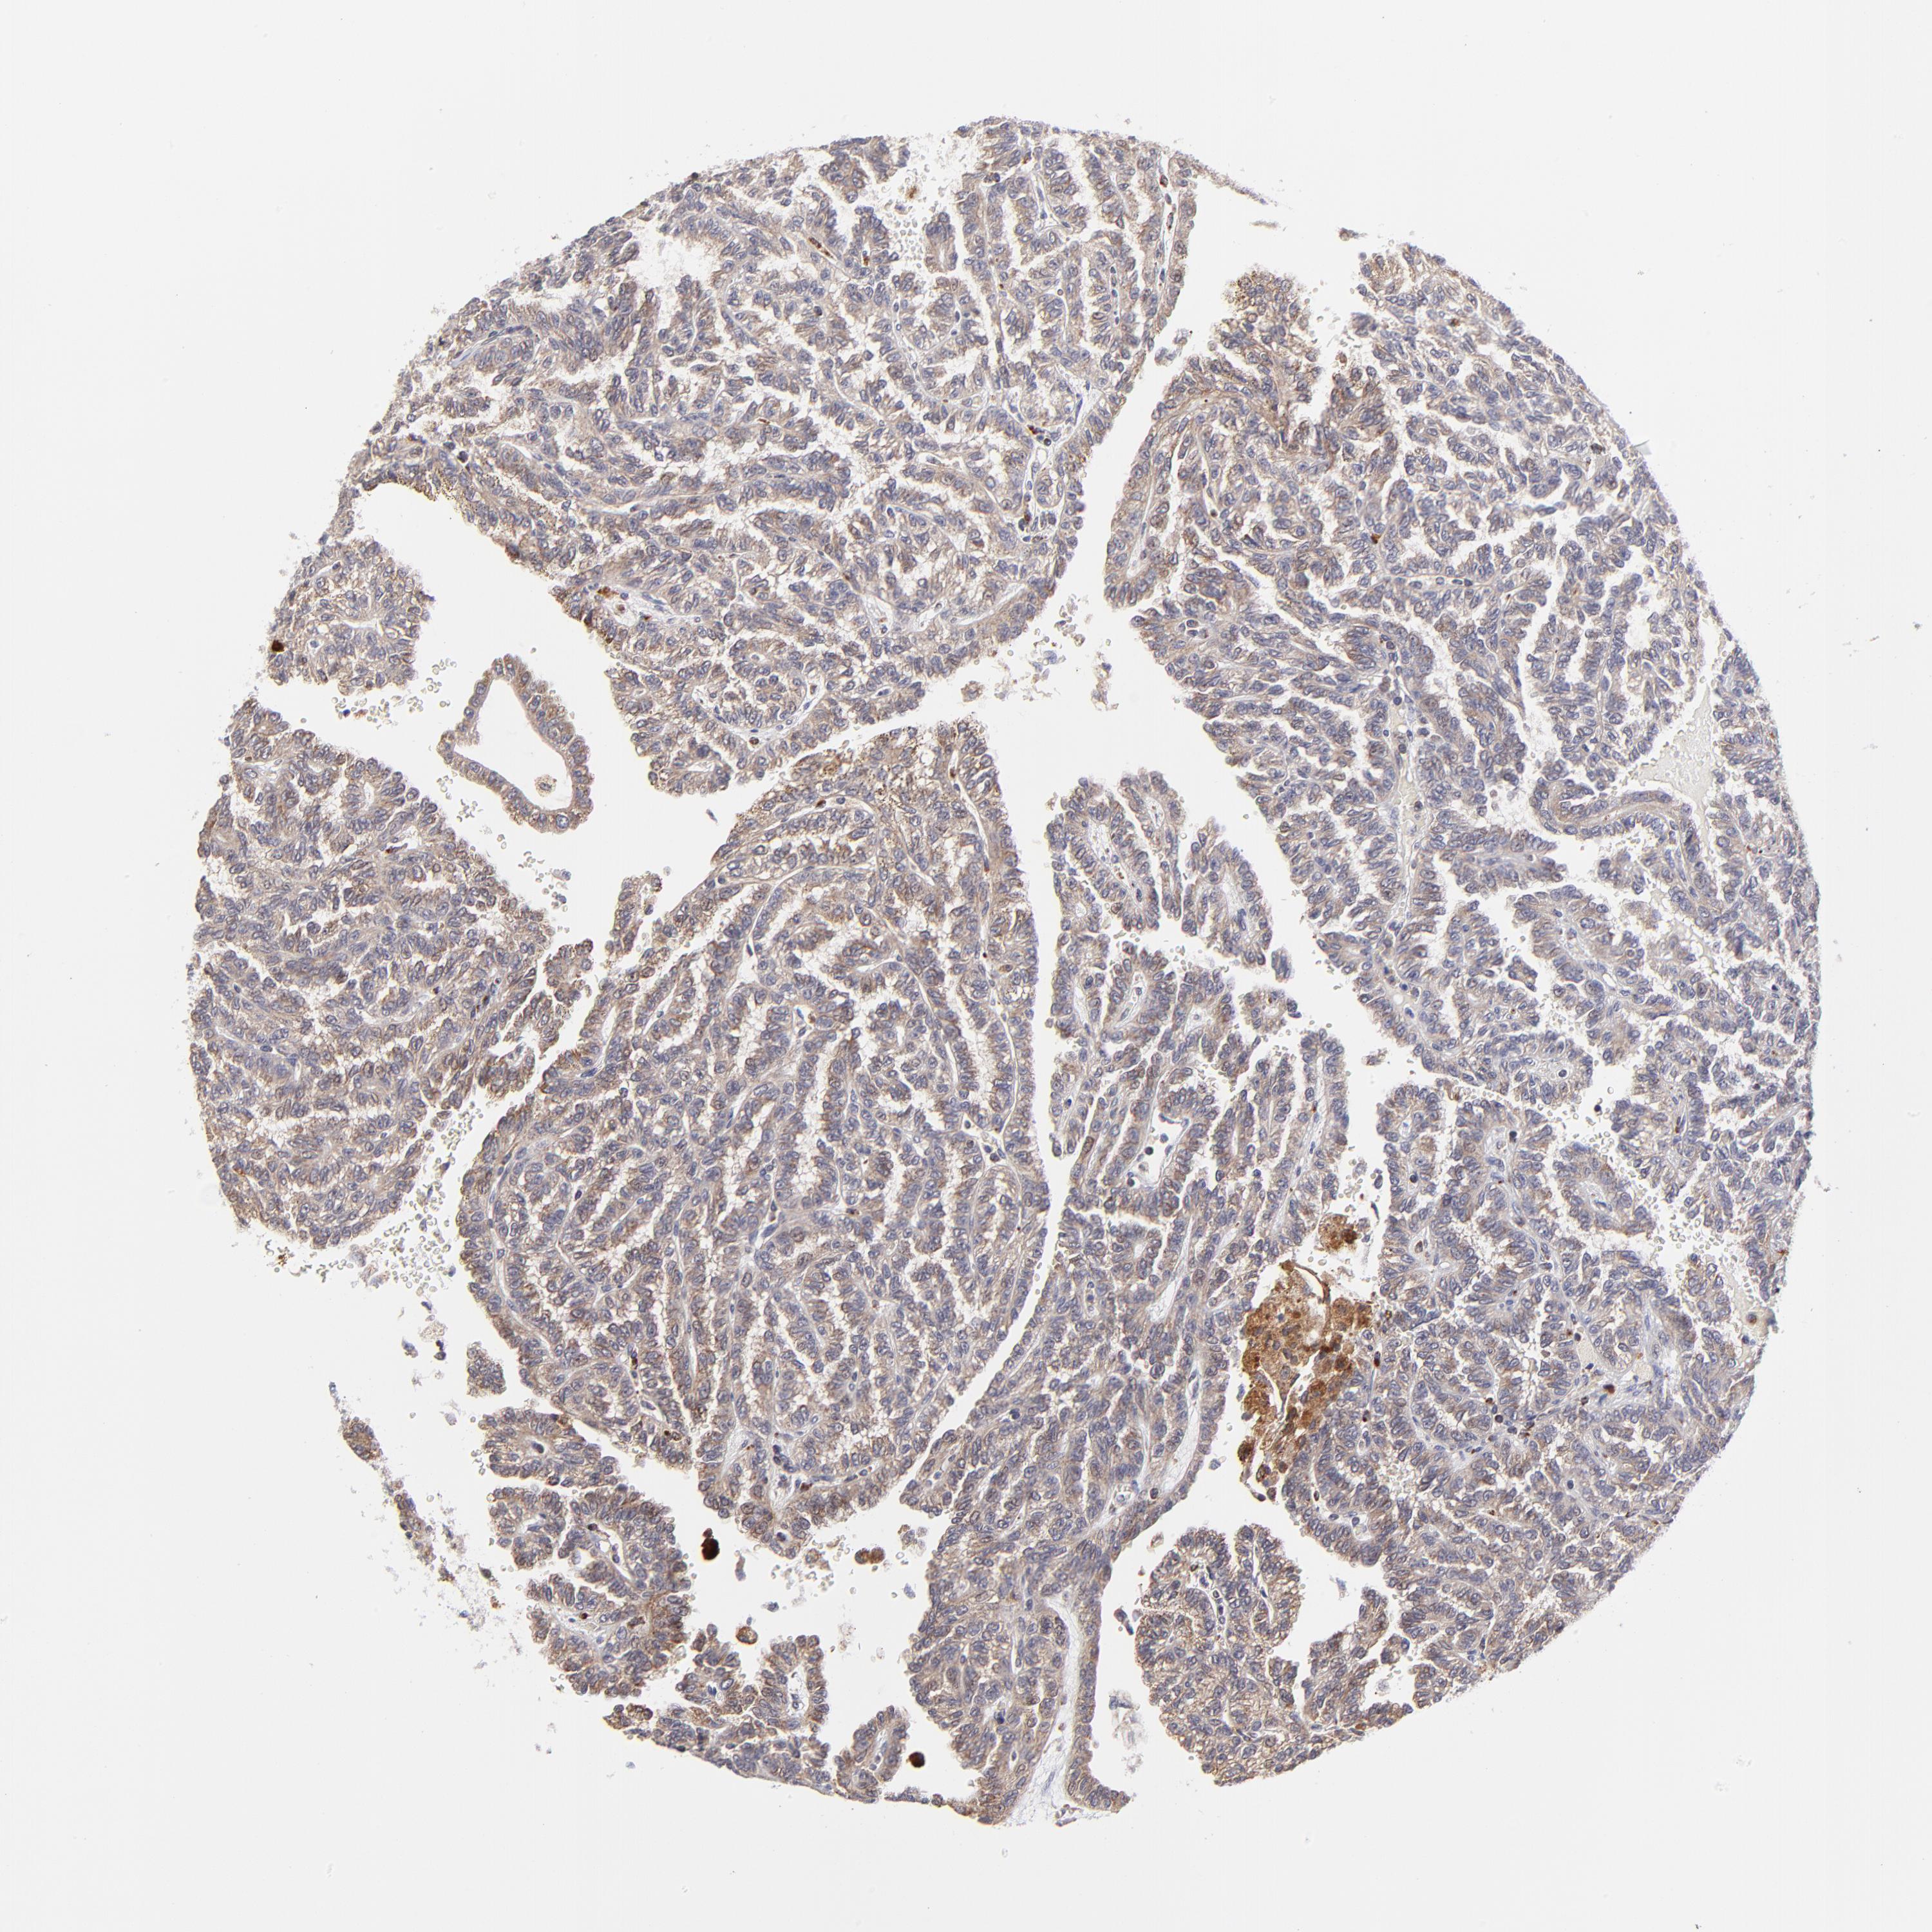

KIDNEY RENAL CLEAR CELL CARCINOMA (VALIDATION) - Interactive survival scatter ploti

The Survival Scatter plot shows the clinical status (i.e. dead or alive) for all individuals in the patient cohort, based on the same data that underlies the corresponding Kaplan-Meier plots. Patients that are alive at last time for follow-up are shown in blue and patients who have died during the study are shown in red.

The x-axis shows the expression levels (FPKM) of the investigated gene in the tumor tissue at the time of diagnosis. The y-axis shows the follow-up time after diagnosis (years). Both axes are complimented with kernel density curves demonstrating the data density over the axes. The top density plot shows the expression levels (FPKM) distribution among dead (red) and alive patients (blue). The right density plot shows the data density of the survived years of dead patients with high and low expression levels respectively, stratified using the cutoff indicated by the vertical dashed line through the Survival Scatter plot. This cutoff is automatically defined based on the FPKM cutoff that minimizes the p-score. The cutoff can be changed by dragging the vertical line or by entering a cutoff value in the square labeled "Current cut-off".

Under the Survival Scatter plot the p-score landscape (black curve; left axis) is shown together with dead median separation (red curve; right axis). Dead median separation is the difference in median mRNA expression between patients who have died with high and low expression, respectively. It is calculated as follows: median FPKM expression of dead patients with high expression - median FPKM expression of dead patients with low expression. This is intended to aid the user in visually exploring custom cutoffs and the associated p-scores and dead median separation.

Individual patient data is displayed and can be filtered by clicking on one or more of the category buttons on the top of the page. Categories describing expression level and patient information include: high, low, alive, dead, female, male and tumor stages. The scale of the x-axis can be toggled between linear and log-scale by clicking on the "x log" button. Mouse-over function shows TCGA ID, patient information and mRNA expression (FPKM) for each patient.

& Survival analysisi

Kaplan-Meier plots summarize results from analysis of correlation between mRNA expression level and patient survival. Patients were divided based on level of expression into one of the two groups "low" (under cut off) or "high" (over cut off). X-axis shows time for survival (years) and y-axis shows the probability of survival, where 1.0 corresponds to 100 percent.

MAP2K7 is not prognostic in Kidney Renal Clear Cell Carcinoma (validation)

Best expression cut offi

Based on the FPKM value of each gene, patients were classified into two groups and association between prognosis (survival) and gene expression (FPKM) was examined. The best expression cut-off refers the FPKM value that yields maximal difference with regard to survival between the two groups at the lowest log-rank P-value. Best expression cut-off was selected based on survival analysis .

When clicking on this number, the vertical dashed line indicating cut-off, the interactive survival plot, and the Kaplan-Meier curve will be adjusted to show results based on the best expression cut-off.

: 15.71

P scorei

Log-rank P value for Kaplan-Meier plot showing results from analysis of correlation between mRNA expression level and patient survival.

N/A

TCGA RNA samplesi

RNA-seq data is reported as average FPKM (number Fragments Per Kilobase of exon per Million reads), generated by the The Cancer Genome Atlas (TCGA) .

Normal distribution across the dataset is visualized with box plots, shown as median and 25th and 75th percentiles. Points are displayed as outliers if they are above or below 1.5 times the interquartile range. FPKM values of the individual samples are presented next to the box plot.

Average pTPM 19.9

Number of samples 100